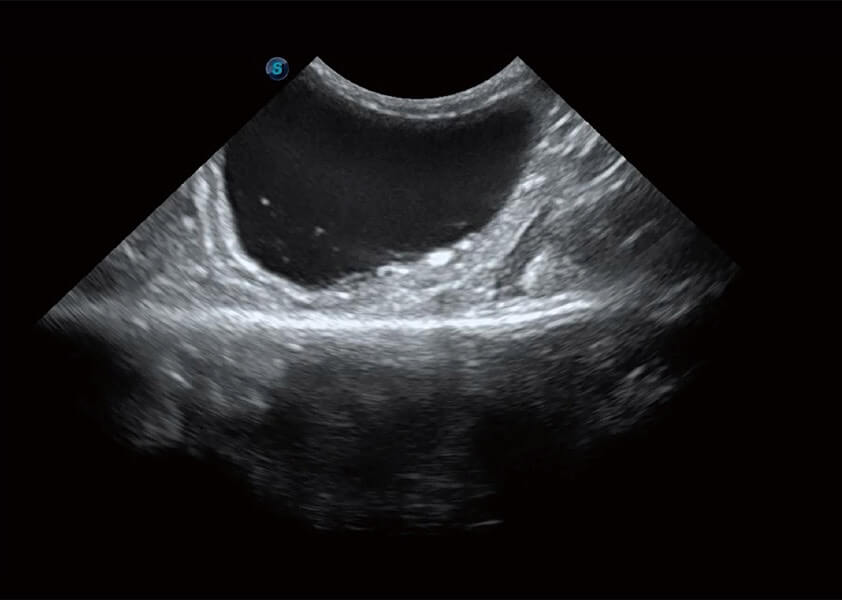

ProPet 60 作為一款高端臺式動物超聲設備,為動物醫(yī)生的日常診斷提供了一系列貼合動物臨床需求、解決臨床實際問題的高級成像功能。憑借全系列高清探頭,滿足醫(yī)生對腹部、心臟、生殖、淺表、肌骨等成像的所有需求,切實幫助您提升檢查效率,提高診斷信心。

獸用彩色多普勒超聲診斷系統(tǒng)